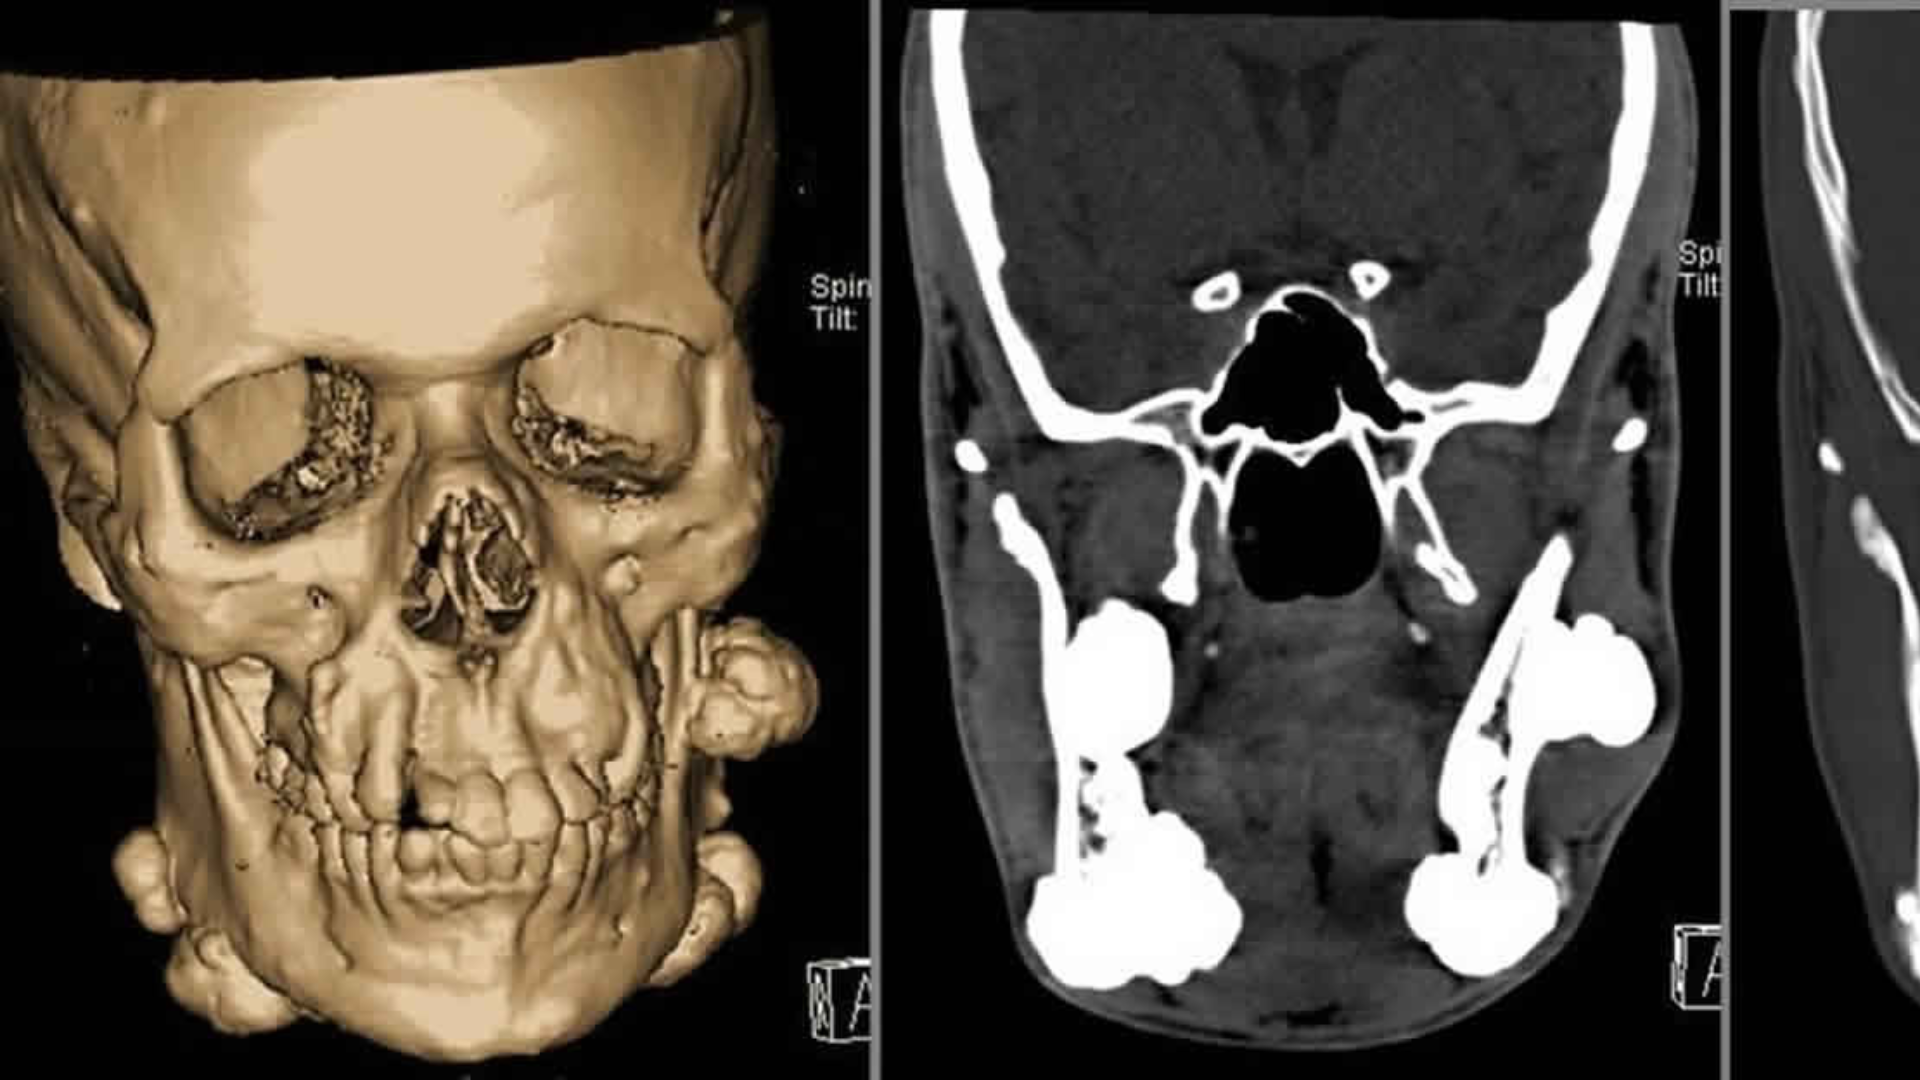

Vì vậy, chẩn đoán hình ảnh qua phim X-quang là bước bắt buộc để phân biệt chính xác các tình trạng này.

Khi đến khám với nghi ngờ có hay không tình trạng mọc 5 răng khôn, người bệnh sẽ được bác sĩ thăm khám lâm sàng trực tiếp để đánh giá tình trạng nướu và cung hàm. Bước tiếp theo là chụp X-quang toàn hàm hoặc phim cắt lớp nếu cần để xác định chính xác số lượng, vị trí và hướng mọc của tất cả các răng trong xương hàm. Dựa trên kết quả, bác sĩ sẽ tư vấn kế hoạch theo dõi hoặc can thiệp phù hợp với từng trường hợp cụ thể.